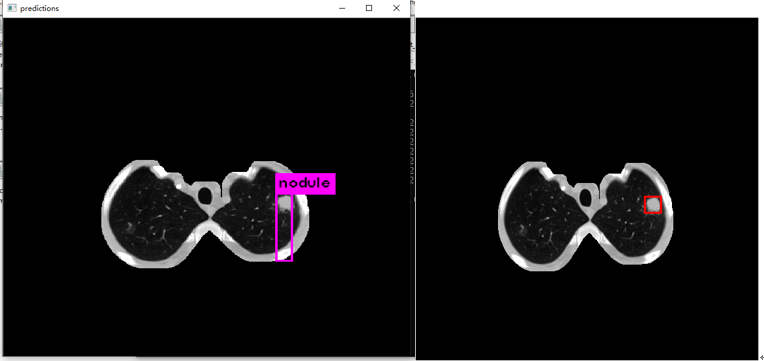

3. 检测效果预览

3.2 训练结果显示

原图:

预测:

标注图(根据标注生成):

在应用yolov3算法进行肺结节检测时,发现其在实际应用中仍存在一定局限性。具体表现为:1)迭代训练不足导致模型尚未达到充分收敛的状态;2)有必要对训练数据集进行聚类分析以优化参数设置,并调整anchor框大小与比例参数设置以进一步提升检测精度。

下图左边是预测,右边是根据标注生成的ground truth。